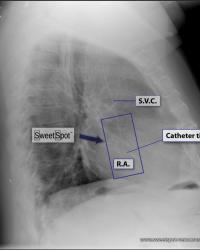

Figure - 11

Left-sided access - The catheter can still be very vertical in S.V.C and R.A. |